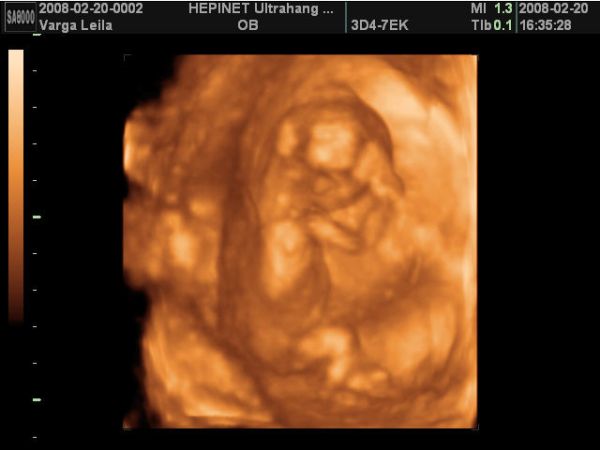

A babó a vizsgálat alatt végig tornázott, izgett-mozgott, úgy nevettem közben, mert annyira jó volt látni, hogy ficánkol, meg homorít a hátával.

A lába között volt a köldökzsinór, és hát eléggé ficánkolt is, úgyhogy csak egyszer láttunk valamit, mikor terpesztett 2D-ben. A nő azt mondta, hogy olyan fiúsnak látszik, de még nem mer biztosat mondani. Szerintem is az lesz, mert én is úgy érzem. De azért a 18. hetin már remélem jól fog látszani.

Aztán a legvégén nagyon befúrta magát a méhfalba, úgyhogy az arcát nem tudtuk jobban megnézni.